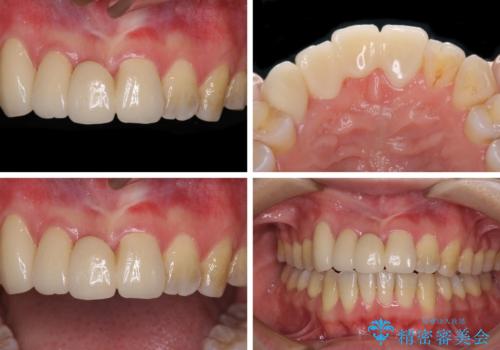

補助装置により上顎歯列を遠心移動させたため、非抜歯でしたが口元の突出感をある程度改善させることができました。

欠けてしまった前歯もオールセラミッククラウンにて自然に補綴することができました。